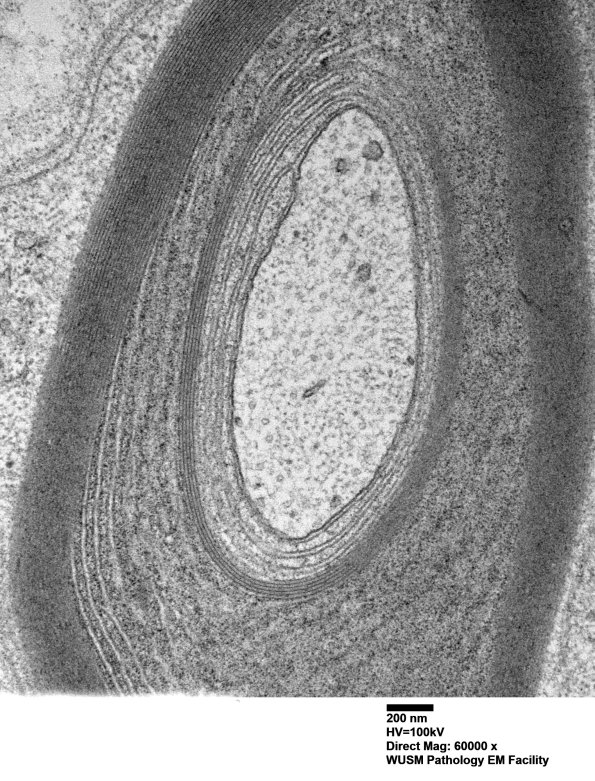

Washington University Experience | PERIPHERAL NEUROPATHY | 13 POEMS SYNDROME | 1B2C (Case 1) Sural_039 - Copy

1B2C (Case 1) Sural_039 - Copy

In some cases the angle of section hides the lamellar change. (electron micrographs)